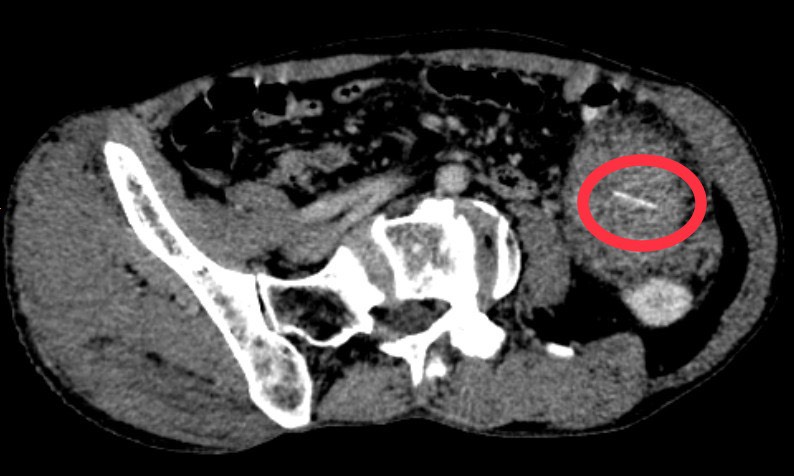

Qua thăm khám, siêu âm và chụp cắt lớp vi tính ổ bụng có tiêm thuốc cản quang cho thấy có khối tỉ trọng hỗn hợp nằm cạnh trước đại tràng trái gồm dịch, mô mềm và phần tăng tỉ trọng kích thước 24 x 0,5mm (nghi ngờ dị vật, xung quanh có thâm nhiễm mỡ). Bệnh nhân được chỉ định phẫu thuật mở ổ bụng gắp dị vật.

Hình ảnh dị vật xương cá trên phim chụp cắt lớp vi tính

BSCKII. Mai Thế Long – Phó trưởng khoa Ngoại tổng hợp 2 cho biết: Khi phẫu thuật các bác sĩ đã thấy được xương cá dài khoảng 3cm, 1 đầu xương cá còn nằm trong lòng đại tràng và 1 đầu đâm thủng đại tràng ra ngoài, được mạc nối lớn bọc lại tạo thành ổ áp xe lớn có nhiều mủ kích thước 15x15cm trong ổ bụng.